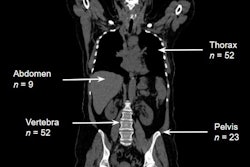

"The bus pulled up and I was taken straight up to the Turkish clinic, where there was an x-ray machine and no one to operate it, but a long queue of patients," Lewis said. "There have been a lot of crush injuries, from people who got trapped in buildings or hit by falling rubble and have then had to make their way to the clinic from some distance away."

Sergeant Lewis attends a patient in Turkey injured in a recent earthquake. Image courtesy of the British Army.The hospital at Türkoğlu where Lewis' regiment is set up had a radiology department with 12 full-time staff before the earthquake struck, according to the post.

"Unfortunately, the building is too damaged to reopen and none of the radiographers have come back to work -- in fact, the first patient I x-rayed was one of the radiographers who had a broken back," Lewis said.